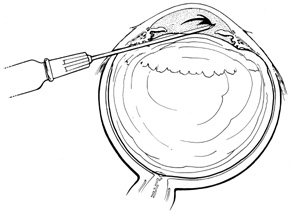

Drainage can be performed via either a radial sclerotomy and external observation of the drainage site, or external needle drainage and indirect ophthalmoscopic observation of the needle in the subretinal space. External needle drainage is technically more challenging. It is performed either with the scleral buckle left loose as originally described by Charles in 198584 or with it tightened to an appropriate height and the sutures permanently tied.85 Using the technique reported by Charles, Burton, and colleagues reported an 84% successful rhegmatogenous retinal detachment repair with one surgery.86 However, subretinal hemorrhage occurred in 22% of cases, and the blood extended subfoveally in four cases. Raising the intraocular pressure by tightening the scleral buckle is thought to mitigate intraocular bleeding. The subretinal hemorrhage rate as described by Jaffe and colleagues was 4%.85 To perform external needle drainage, the surgeon uses a 0.5-inch 25-, 26-, or 27-gauge needle attached to a tuberculin, 3- or 5-cc syringe with the plunger removed. The authors prefer the larger gauge needles because these do not bend easily when scleral depressing or while angling the needle to enter the eye. The authors also prefer the larger volume syringe to minimize the water pressure within the syringe. A tuberculin syringe holding its maximum of 1 mL of fluid has more pressure and therefore resistance to drainage when held vertically, compared to a 5-cc syringe. Consequently, more subretinal fluid can be drained with a larger volume syringe before equilibrium exists between the water pressure of the syringe and the intraocular pressure.

The bevel of the needle is directed away from the sclera. With the needle shaft tangential to the sclera to prevent premature scleral penetration, scleral depression is performed to confirm the correct location for drainage. When the correct location is found, the syringe is angled away from the eye and the needle is passed through the sclera and choroid into the subretinal space. The surgeon directly observes the needle with indirect ophthalmoscopy as it passes into the subretinal fluid. The detached retina immediately begins to undulate, signifying that subretinal fluid is leaving via the needle. Pressure must be maintained during the drainage, either by the tightened scleral buckle or by an assistant pulling on the rectus muscle bridle sutures or depressing the sclera. Pulling on the rectus muscle or scleral depression may result in movement of the globe if not done carefully. Any movement makes proper needle position difficult. Such movements are eliminated when the scleral buckle is pretightened. As the retina settles and nears the drainage needle, the needle is slow withdrawn until it is removed from the subretinal space. If the retina is inadvertently penetrated, retinopexy should be applied to the site. If the eye is hypotensive after the drainage, it can be reformed with balanced saline, air, or expansile gas.